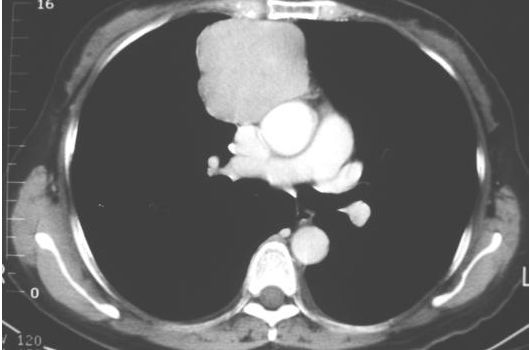

11. 一位66歲男性,主訴呼吸困難有二個月,胸部影像如圖(圖a,圖b)。他的肺功能檢查結果可能顯示何種變化?

1. VC正常或↑ , 2. RV ↑ , 3. RV/ TLC ↓ , 4. FEV1 / FVC 正常或↑ , 5. DLco ↓

圖a

圖b

(A) 1 + 3 (B) 1 + 4 (C) 2 + 4 (D) 2 + 5 (E) 4 + 5